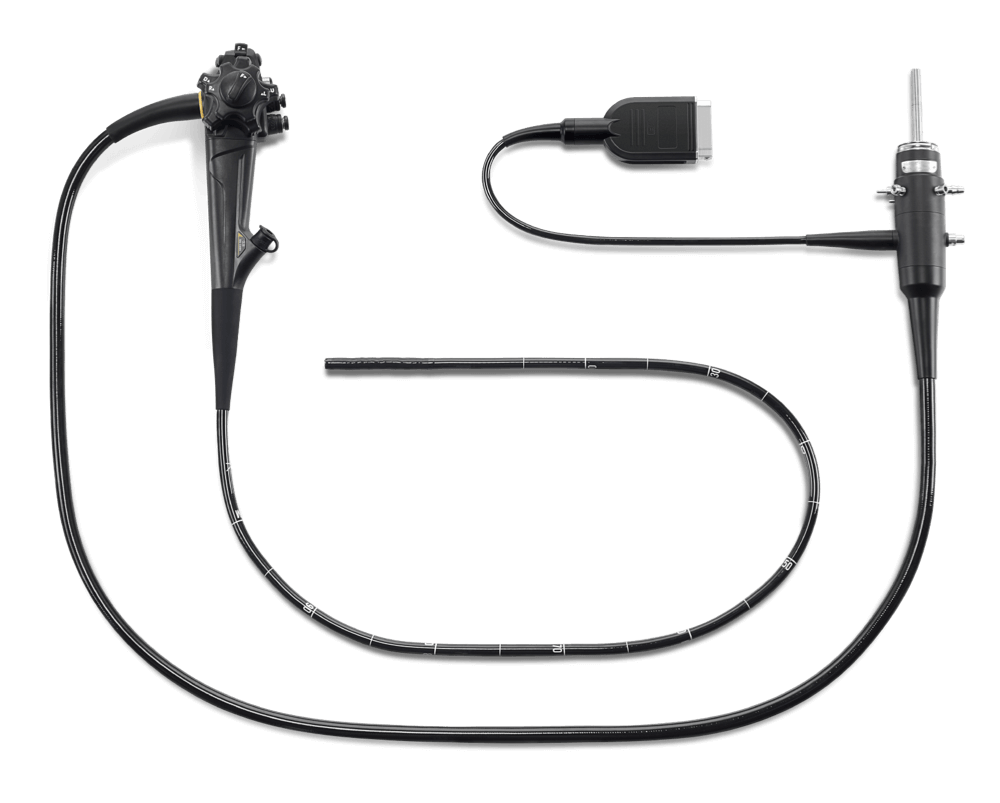

X-2200pro

高清电子内镜系统

高清电子内镜系统

精巧的设计,独具匠心的功能赋予全系列内镜出色的操作体验。 坚持做好每一个细节,只为让您的诊治更加舒心。

轻量化手柄,减轻操作者长期持镜的疲劳。

无需断电直接插拔镜体,减少步骤,提升效率,降低镜体损坏风险。

可直接浸泡洗消无需防水帽,避免了因为误操作而导致的进水损坏的风险。

视野方向: 直视(0°)

视场角: 140°

观察景深: 3-100mm

弯曲角度(向上/向下): 210°/90°

弯曲角度(向左/向右): 100°/100°

头端部外径: 9.3mm

插入部主软管外径: 9.3mm

最小器械孔道内径: 2.8mm

有效长度: 1050mm

辅助送水管道: 有